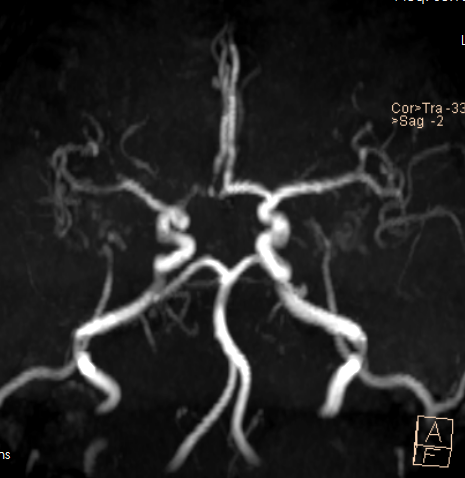

Segmentation of the liver and other vessels. (Source: TCIA Database (see references))